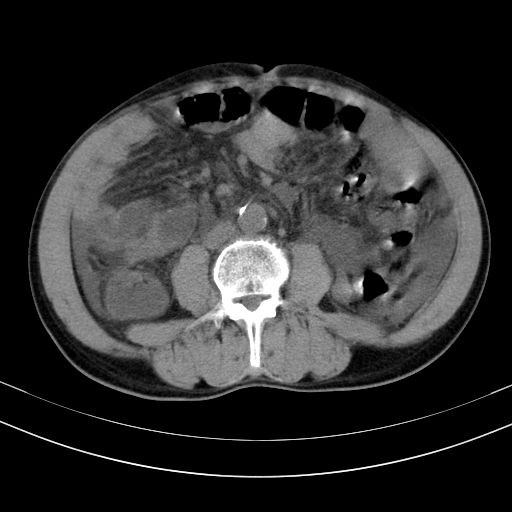

以下是引用随光逐影在2010-2-28 10:23:00的发言:[br]1)考虑肝癌;建议行ct增强扫描检查。2)肝硬化,脾大,腹水。3)慢性胆囊炎。